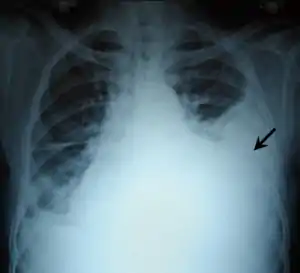

| Chest X-ray showing left sided hemothorax (arrowed) | |

Chest X-ray

A chest X-ray is the most common technique used to diagnosis a hemothorax.[23] X-rays should ideally be taken in an upright position (an erect chest X-ray), but may be performed with the person lying on their back (supine) if an erect chest X-ray is not feasible. On an erect chest X-ray, a hemothorax is suggested by blunting of the costophrenic angle or partial or complete opacification of the affected half of the thorax. On a supine film the blood tends to layer in the pleural space, but can be appreciated as a haziness of one half of the thorax relative to the other.[5] A small hemothorax may be missed on a chest X-ray as several hundred milliliters of blood can be hidden by the diaphragm and abdominal viscera on an erect film. Supine X-rays are even less sensitive and as much as one liter of blood can be missed on a supine film.[24]